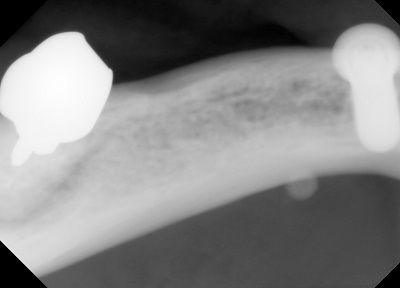

東京歯科大学愛知県同窓会学術講演会

CAD/CAM冠の問題点

オールセラミッククラウンによる接着について